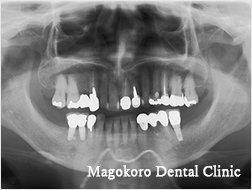

症例は両側の第一大臼歯の欠損に対してインプラント治療を行った症例です。